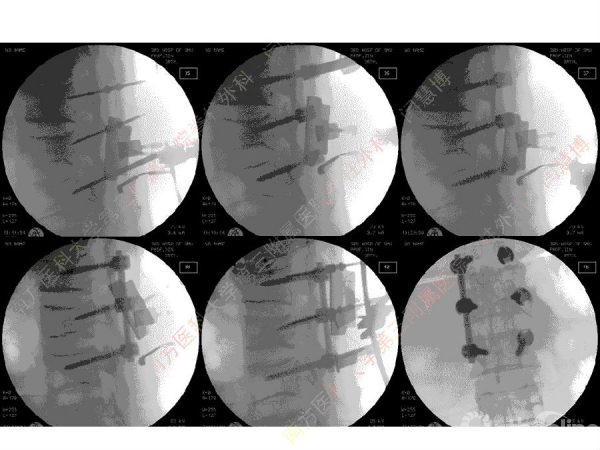

胸腰椎骨折是指由于外力造成胸腰椎骨质连续性的破坏,在如车祸、高处坠落等意外事故中,是最常见的脊柱损伤。老年患者由于本身存在骨质疏松,甚至有可能因为一些如滑倒、跌倒等低暴力因素导致胸腰椎骨折。胸腰椎骨折患者常合并神经功能损伤,且由于致伤因素基本为高能损伤,常合并其他脏器损伤,这为治疗带来了极大的困难和挑战。针对胸腰椎骨折,南方医科大学第三附属医院闫慧博教授介绍了他们运用微创方法治疗的经验。